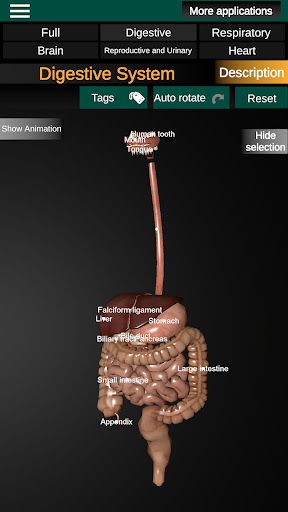

* Spijsverteringsstelsel, inclusief de maag, dunne darm, dikke darm, en een animatie van dit systeem.